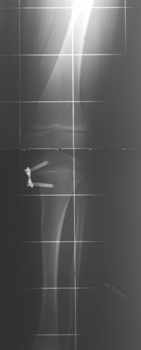

Teleskopnagelung in der Osteogenesis imperfecta-Behandlung

Bei der operativen Behandlung steht die Versorgung von Knochenbrüchen oder Achsfehlstellungen mit Teleskopnagelungen im Vordergrund. Aus orthopädischer Sicht ist trotz ständiger Bruchgefahr viel Bewegung wichtig, um eine stützende Muskulatur aufzubauen und Skelettveränderungen vorzubeugen bzw. zu verzögern.